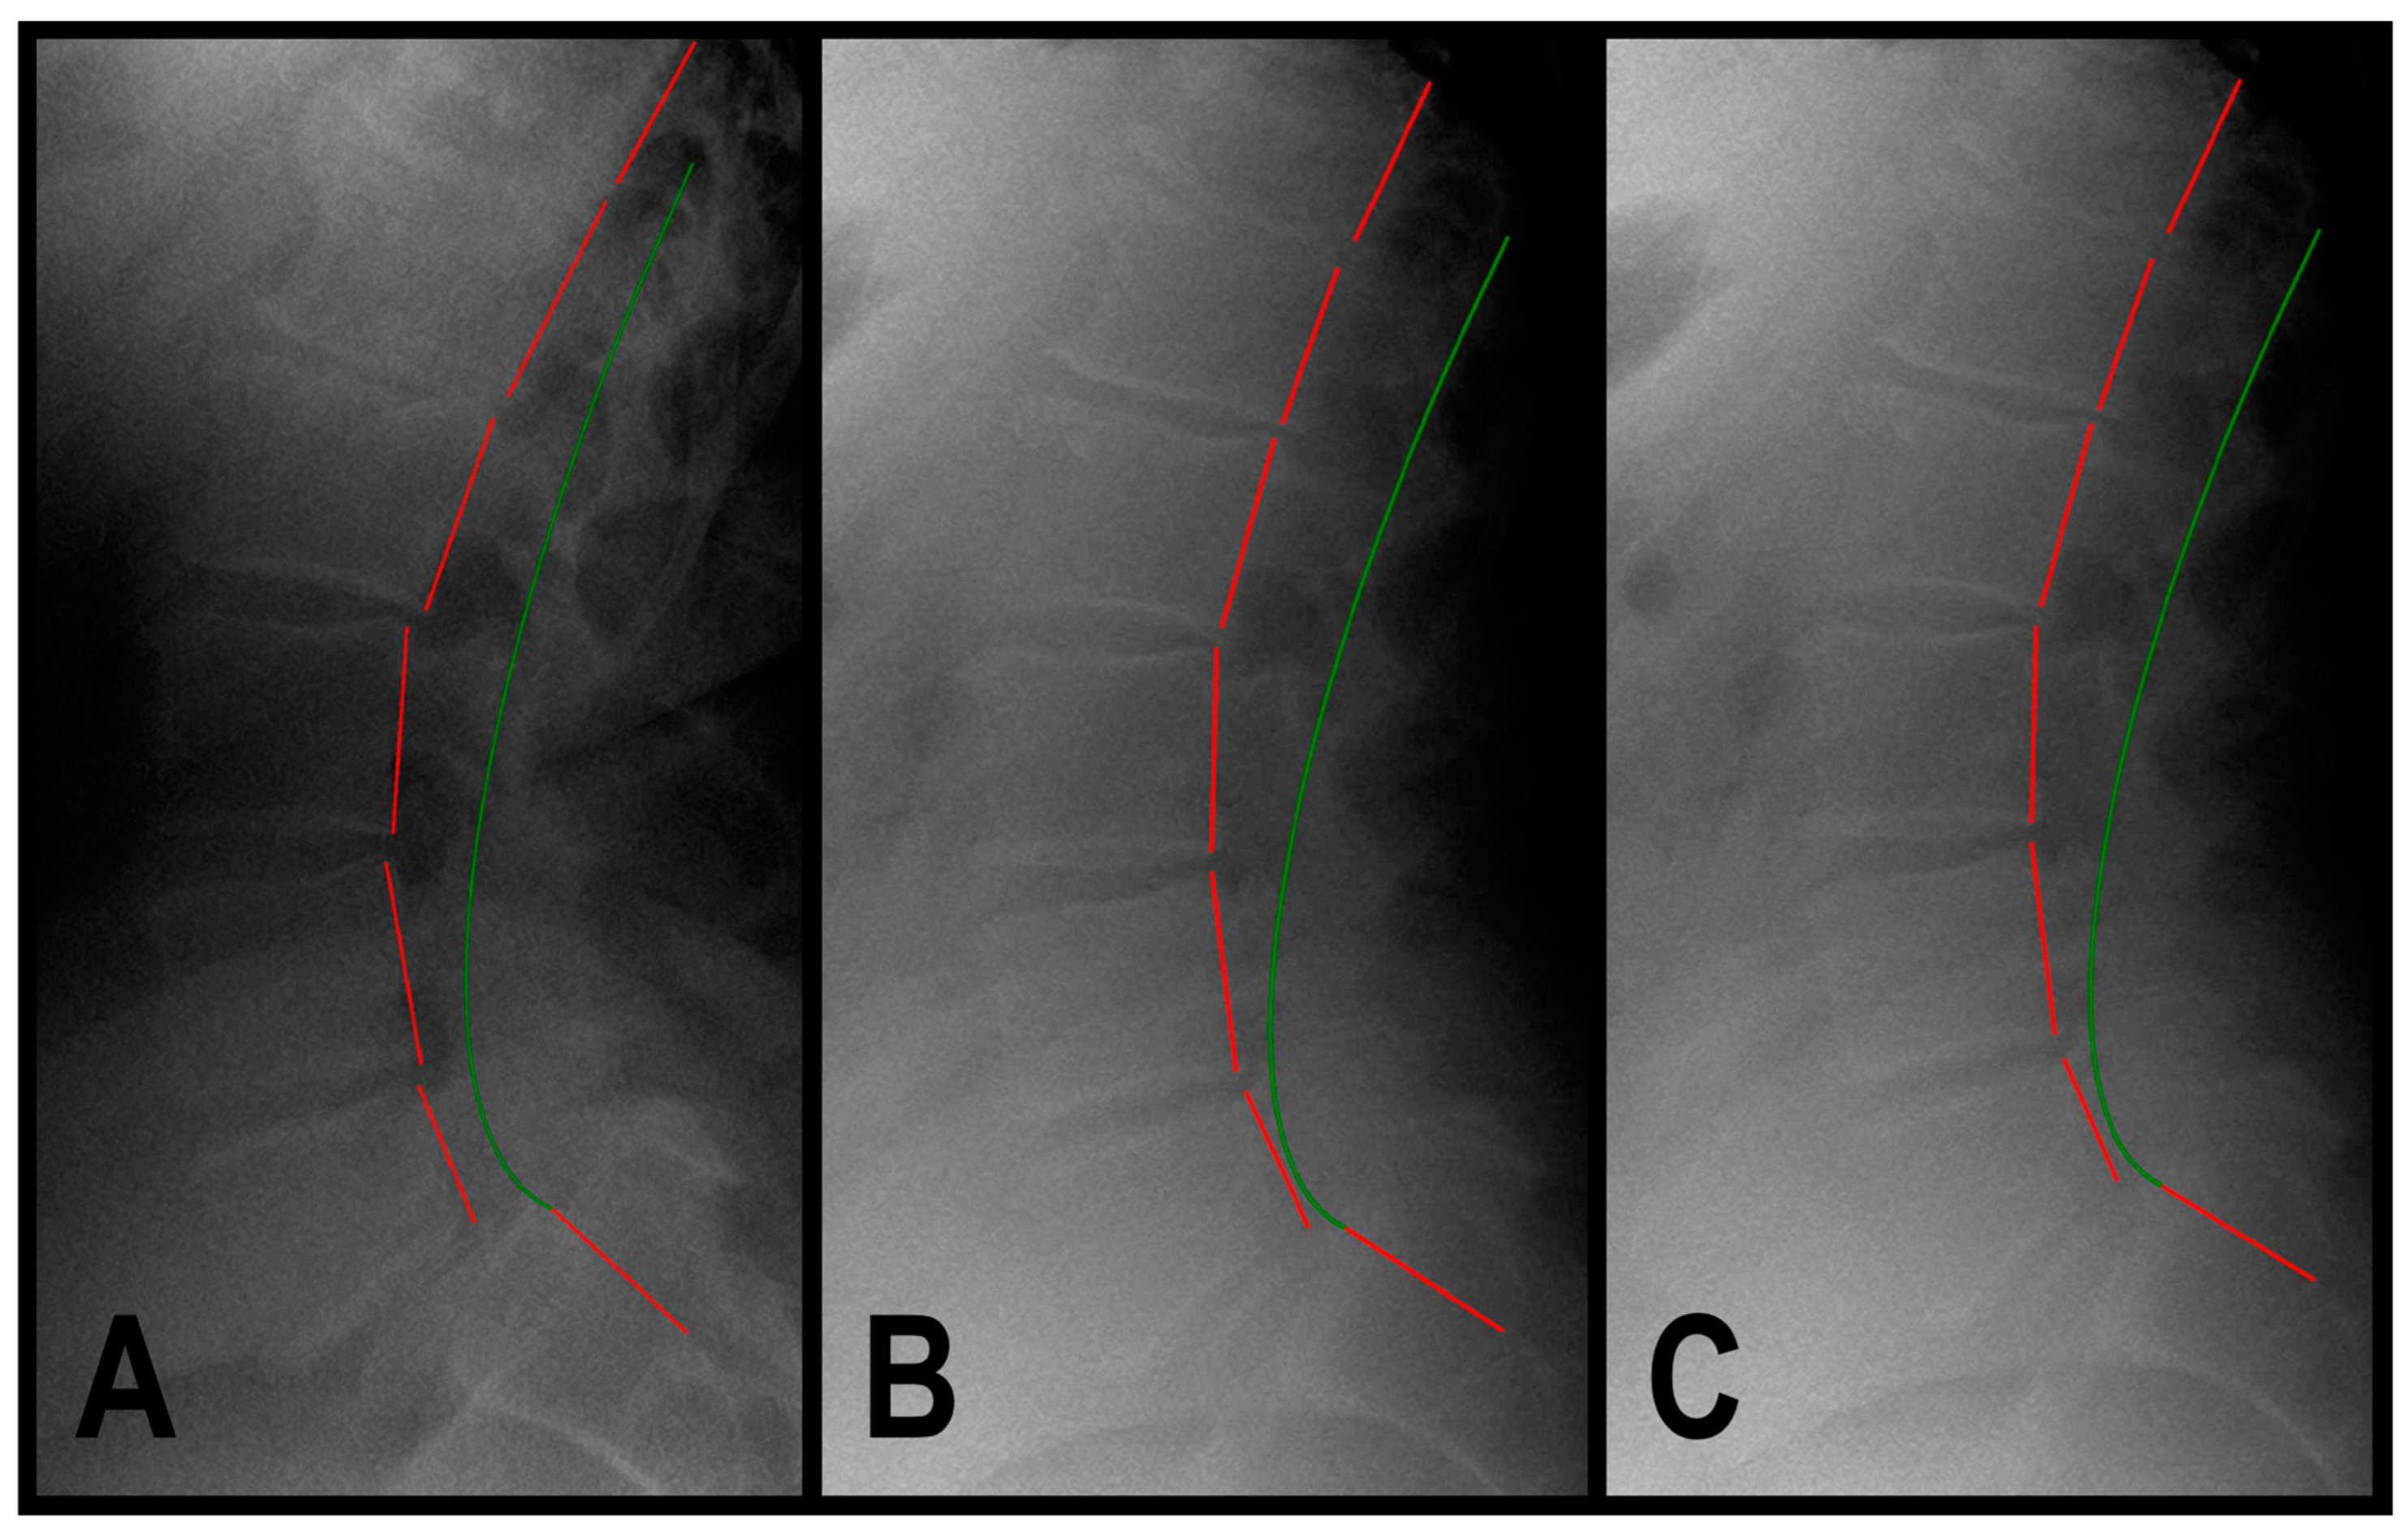

2.3. Radiographic Analysis

3.1.1. Patient 1

3.1.2. Patient 2

3.1.3. Patient 3

| Assessment | Normal Value | Pre-Treatment Exam 2/2022 | Post-Treatment Exam 5/2022 | 1.25-Year Follow-Up Exam 8/2023 | |

|---|---|---|---|---|---|

| Back Pain NRS | 0 | 8 | 1 | 2 | |

| SF-36 HRQOL Scales | PF | 72.0 | 0.0 | 55.0 | 55.0 |

| RP | 81.0 | 0.0 | 100.0 | 100.0 | |

| RE | 81.0 | 0.0 | 100.0 | 100.0 | |

| VT | 61.0 | 15.0 | 80.0 | 75.0 | |

| MH | 81.0 | 80.0 | 100.0 | 80.0 | |

| SF | 83.0 | 25.0 | 75.0 | 100.0 | |

| BP | 75.0 | 22.5 | 70.0 | 62.5 | |

| GH | 72.0 | 67.5 | 90.0 | 90.0 | |

| ΔH | 84.0 | 25.0 | 100.0 | 75.0 | |

| PCS | 46.8 | 21.8 | 44.1 | 45.4 | |

| MCS | 52.8 | 42.2 | 62.7 | 60.1 | |

| ARA L1-L5 (°) | −40 | −49.9 | −42.2 | −43.6 | |

| Tz L5-S1 (mm) | 0 | 13.8 | 4.2 | 4.3 | |

| Urination Frequency (times/24 h) | 0 | 12 | 6 | 6 | |

| Urinary Urgency NRS | 0 | 9 | 3 | 3 | |